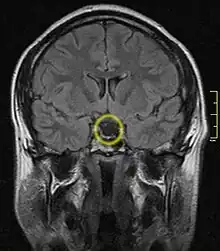

Empty sella turcica on MRI as seen in severe cases of Sheehan's syndrome

MRI is useful in diagnosing Sheehan's syndrome since it examines the structure of the pituitary and may identify any anatomical damage.[4] MRI findings will vary based on how early or late in the disease process the test is being conducted. If an MRI is conducted early enough in the disease process the pituitary may appear larger than normal, and show changes that are consistent with damage from lack of blood supply.[15] Later in the disease process of this syndrome the damage imposed on the pituitary gland will cause it to shrink, and leave a partially empty or totally empty sella turcica on MRI.[7]